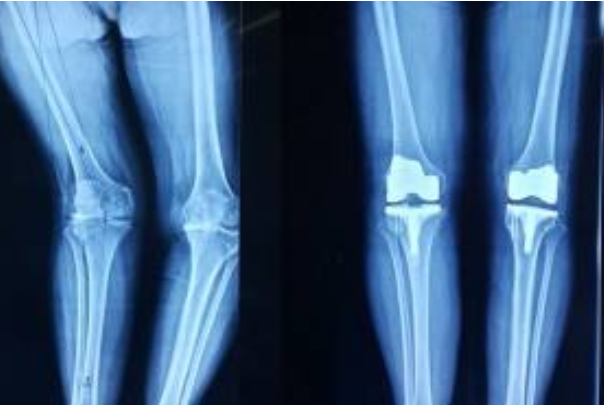

用于人工骨和人工关节的碳纤维

Invibio公司是医疗器械的知名供应商,它所开发的短切碳纤维增强聚醚醚酮(PEEK),具有优良的力学强度和抗拉蠕变性,可承载骨头、血液及人体组织所需的负荷,与人体的相容性良好。这种人工骨的抗弯曲强度较其他生物材料制成的人工骨,更接近于真实的人骨,这对矫形医学意义重大。用它制成的人工关节在活动连接处的耐磨性也比超高相对分子质量聚乙烯及金属制品要高。